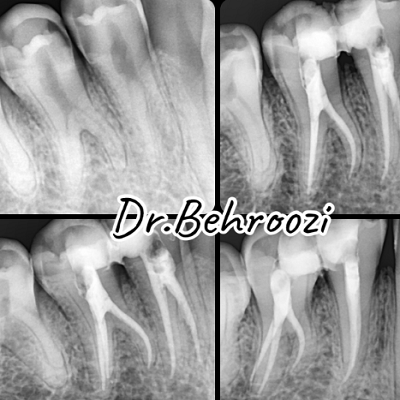

روش درمان ریشه دندان شامل چند مرحله اساسی است که ابتدا با تصویربرداری دقیق دندان، تشخیص و تعیین محل عفونت صورت می گیرد. سپس با استفاده از دستگاه های خاص و ابزارهای پزشکی، پالپ دندان (عصب) حذف شده و کانال ریشه تمیز شده و آماده پر شدن می شود. در مرحله بعد، کانال ریشه با مواد ضدعفونی پر شده و سپس دندان با چسب مخصوص بسته می شود.

دکتر روح اله بهروزی

دکتر روح اله بهروزی، نفر اول علوم پایه پزشکی جزء یکی از بهترین و کاربلد ترین و ماهر ترین دندانپزشکان در همدان محسوب می شوند. ایشان عضو انجمن دندانپزشکی عمومی، انجمن دندانپزشکان ایران با کد 141732 و انجمن ایمپلنتولوژی ایران می باشند. وی تاکنون توانسته است با ارائه بهترین خدمات به بیماران خود رضایت بالایی را دریافت کنند.

- درمان ریشه دندان های دائمی

- عصب کشی دندان

- کشیدن دندان عقل و جراحی آن

- درمان عفونت ریشه